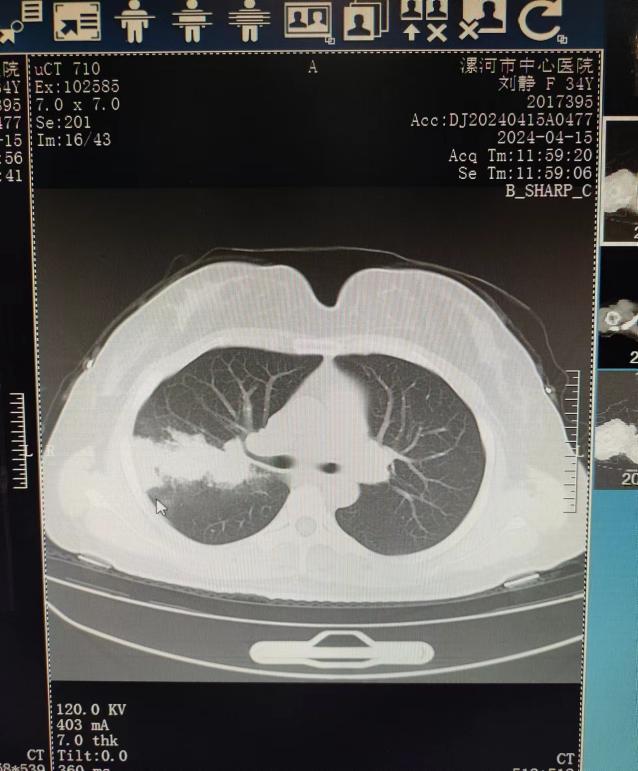

病例:王女士,反复咳嗽、咳痰2年,加重伴喘息2月余。既往曾诊断支气管扩张。曾行肺功能检查提示支气管激发试验阳性。近期于我院住院治疗。胸部CT如下:

因近期再次出现咳嗽、咳痰伴喘息就诊于我院。辅助检查:既往烟曲霉皮肤点刺试验阳性,血清总IgE升高(>2500U/ml),影像学可见指套征、支气管扩张、痰栓,两次外周血嗜酸粒细胞百分比明显升高(1.4-1.5*109/L)升高,支气管镜下可见右上叶及右中叶大量痰栓,BALF NGS提示黄曲霉,变应性支气管肺曲霉病(ABPA)诊断明确。给予针对性治疗数日,韩女士的症状改善后出院。